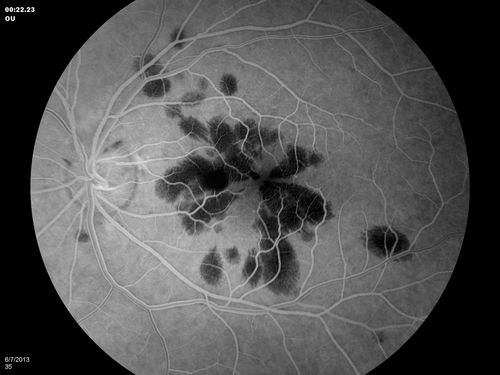

Unilateral Hemorrhagic Retinopathy